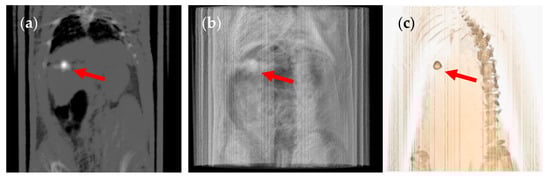

3. Results and Discussion